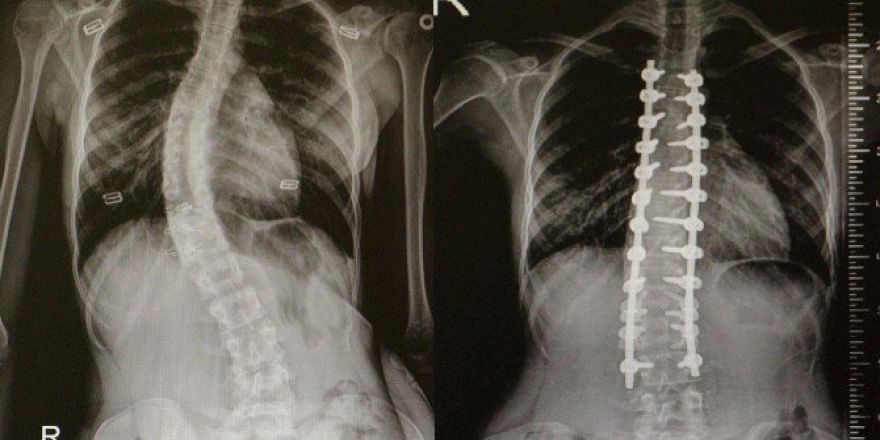

Omurga Eğriliği Olanlar Omü’de Şifa Buluyor